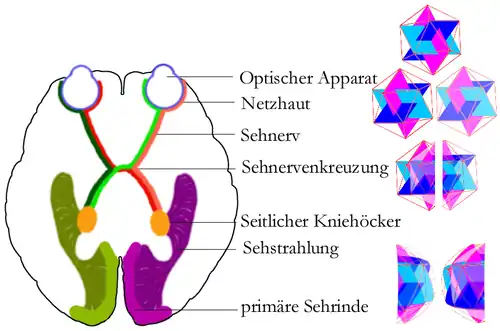

Melanin spielt auch bei der Entwicklung der Sehnerven eine Rolle. Normalerweise ist das Gesichtsfeld beim Menschen unter beiden Gehirnhälften gleichmäßig aufgeteilt – jede Gehirnhälfte hat ihre Seite und bekommt von beiden Augen den Teil des Bildes geliefert, der zu dieser Seite gehört (Sehbahn). Durch den Vergleich beider Bilder kann jede Gehirnhälfte die Entfernung der Gegenstände berechnen und räumlich zuordnen (stereoskopisches Sehen). Bei Menschen mit Albinismus kreuzt ein größerer Anteil der Sehnerven zur gegenüberliegenden Gehirnhälfte, wodurch ein Verlust der physiologischen Nachbarschaft homologer Netzhautareale eintritt und zusammengehörige Bilder nicht immer auf derselben Seite verarbeitet werden.